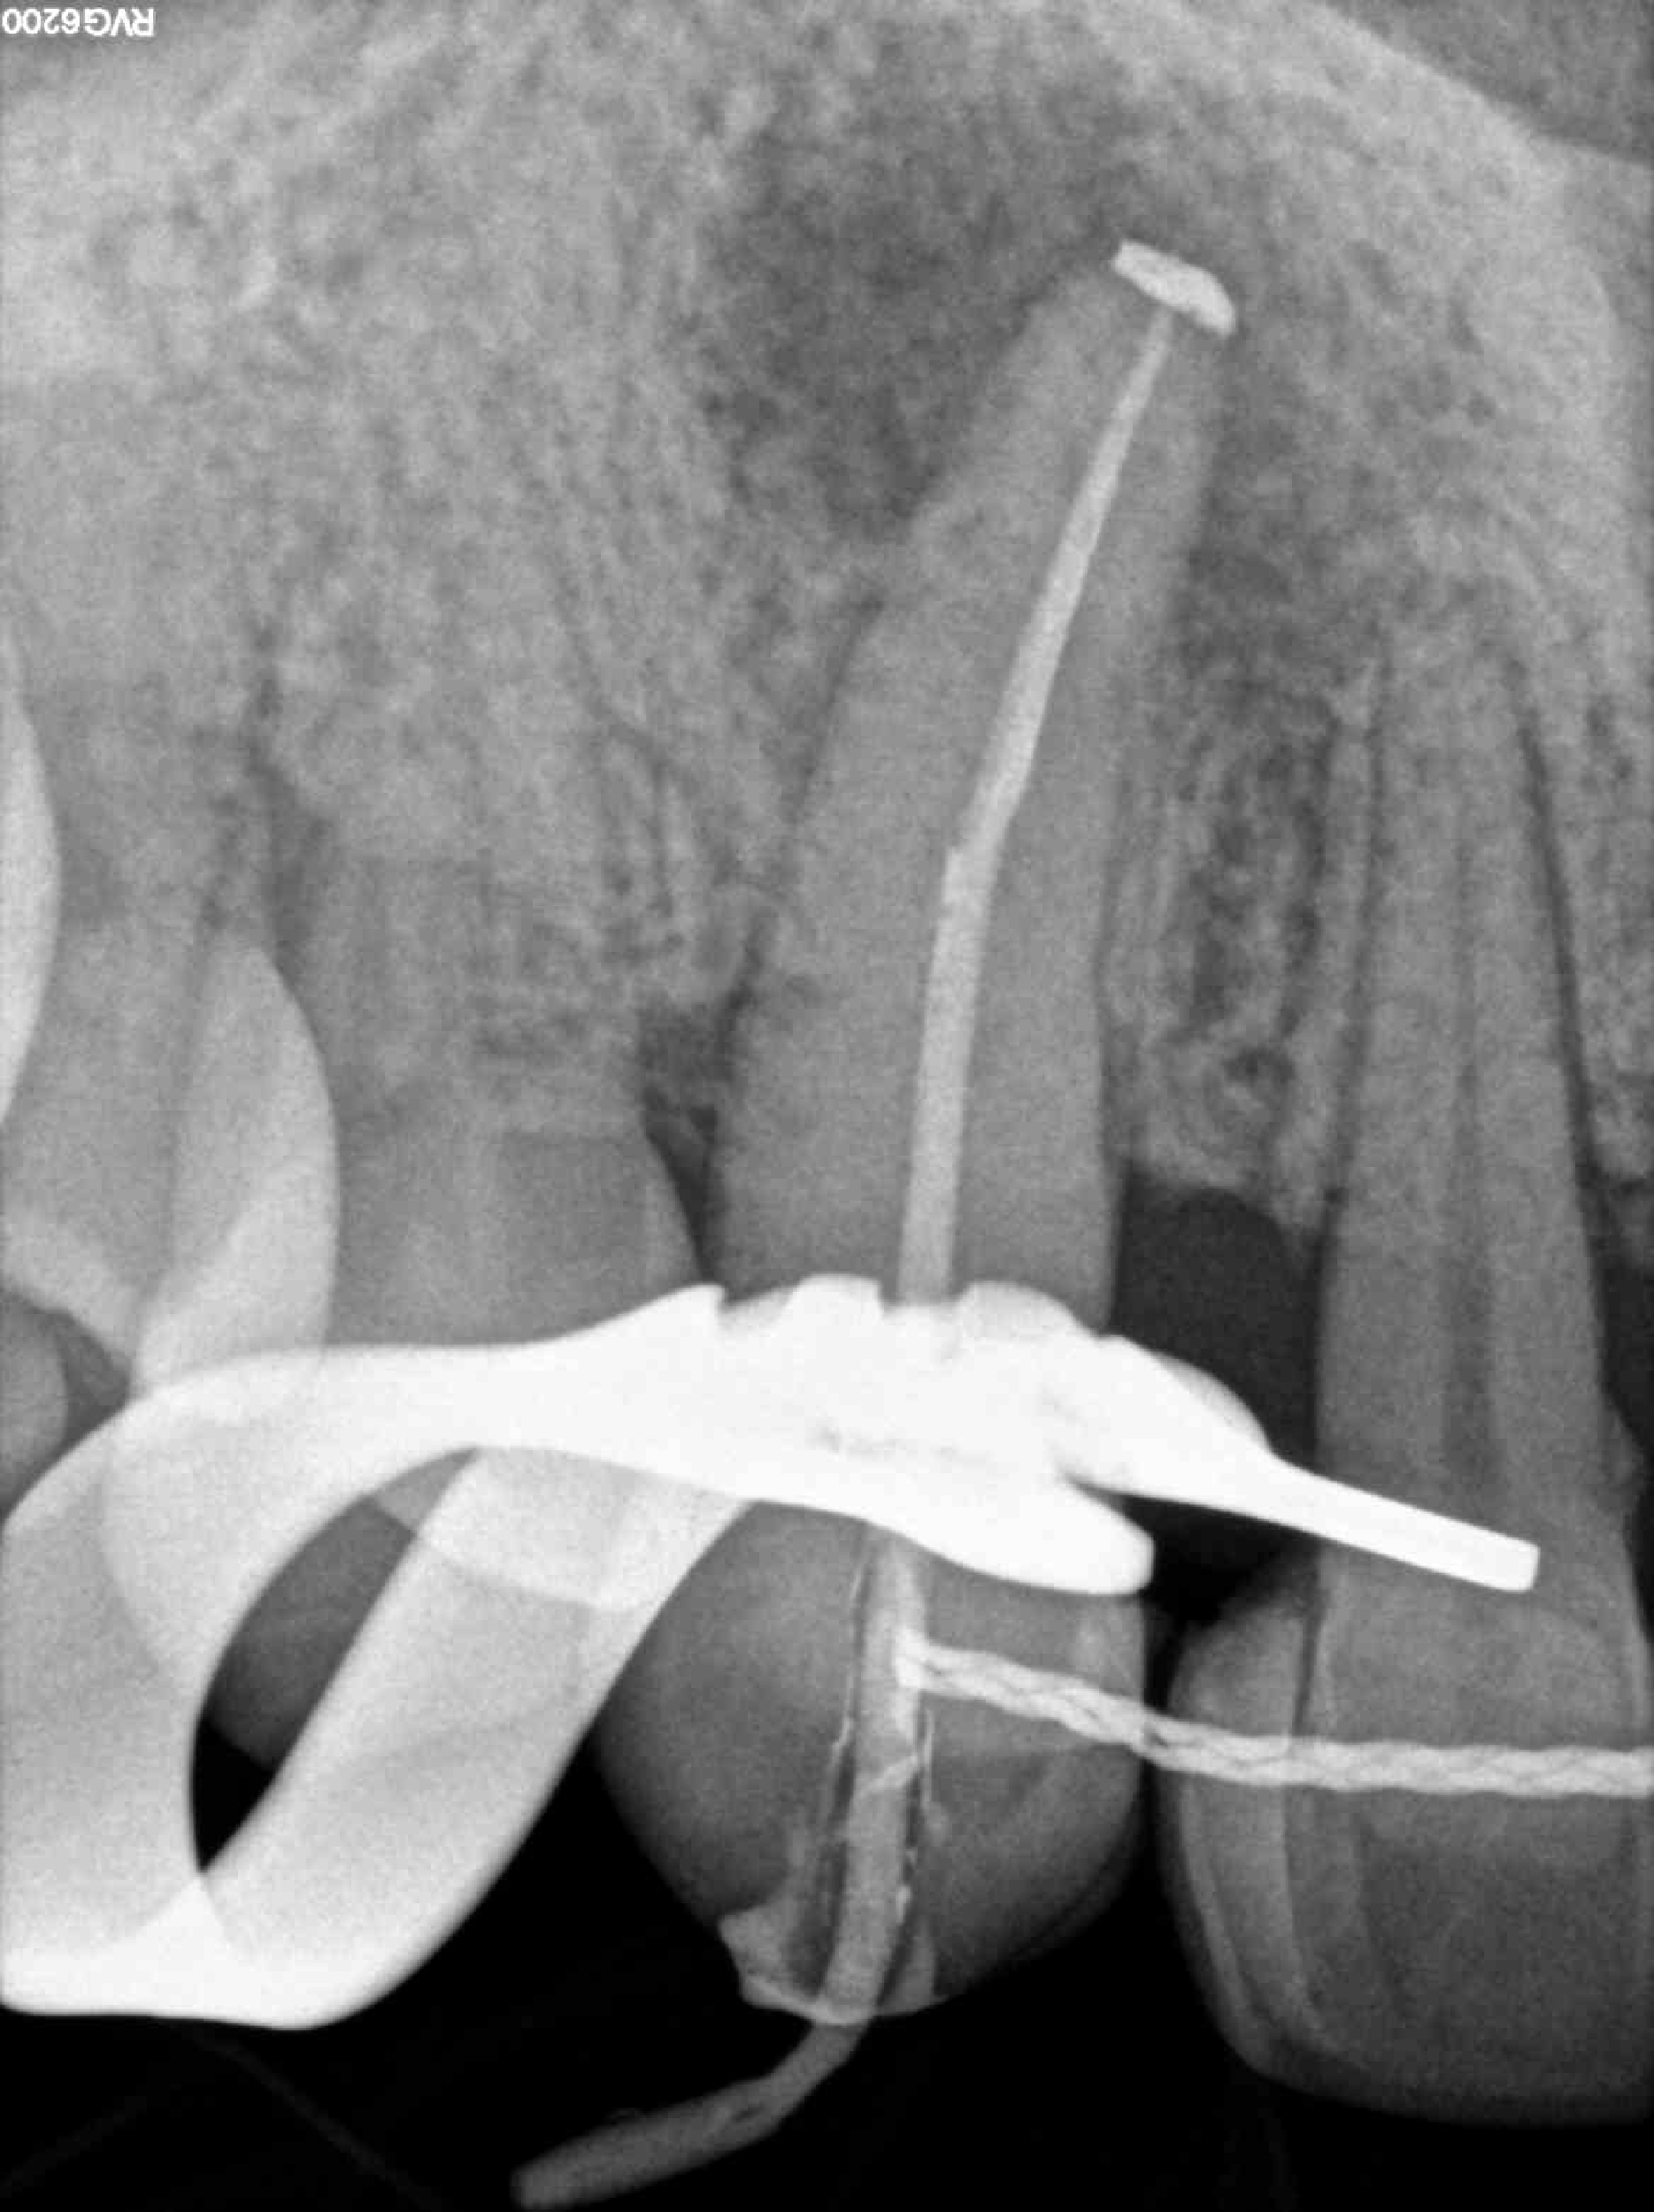

Radiografías

* Haz click sobre las radiografías para verlas a mayor tamaño